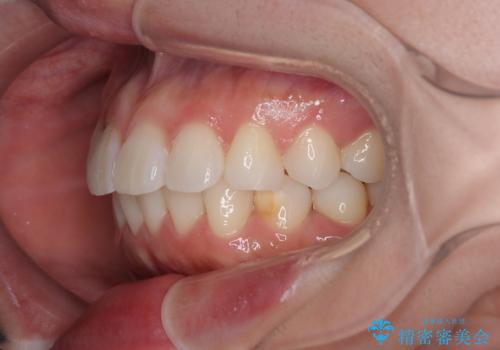

- 上下前歯の叢生を気にして来院された患者様です。

軽度な叢生であり、安価で短期間の治療を規模されていたため、インビザライン・モデレートを用いて矯正治療を行うこととしました。

インビザライン・モデレートは、製作できるアライナーの枚数に制限があるため、移動可能な量に限りがあるものの、インビザライン・ライトよりも枚数が多いため、幅広い症例に対応可能です。